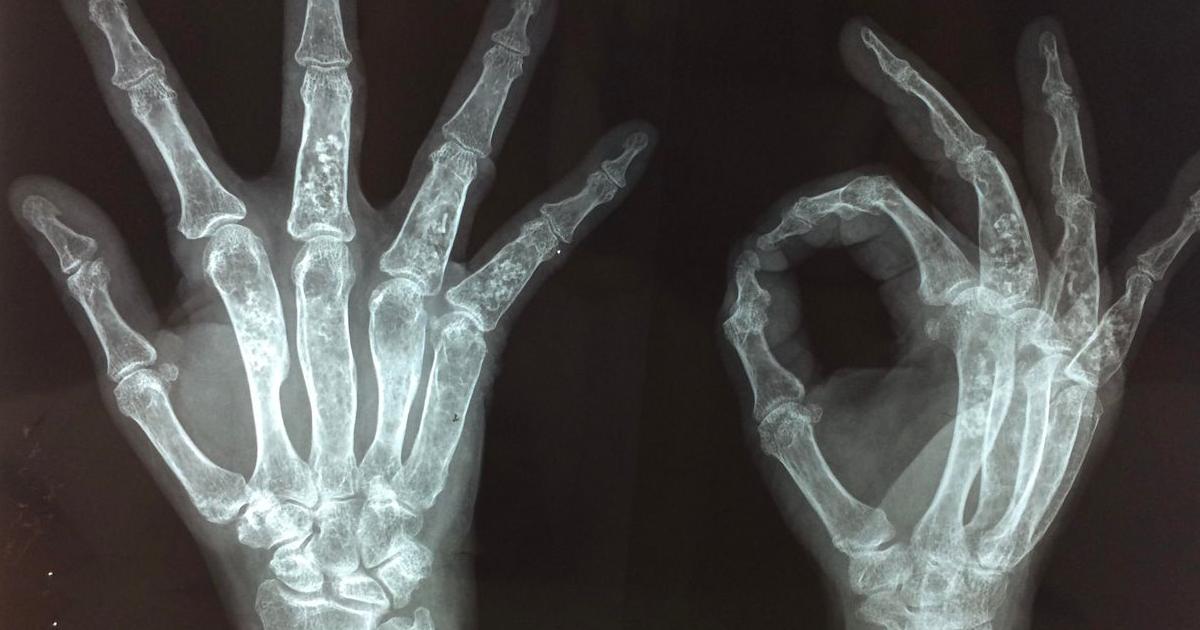

Maffucci Syndrome

Photo Credit: OrthoBullets

Maffucci syndrome is a disorder where multiple benign or noncancerous cartilage growths develop inside of the bones, and purplish or red growths develop in the skin. Much like Ollier disease, Maffucci syndrome is caused by a gene mutation, and individuals affected by it are at a higher risk of developing chondrosarcoma. Maffucci syndrome enchondromas develop near the part of the bones where growth typically occurs. Benign tumors usually stop becoming larger when the individual with Maffucci syndrome stops growing. While it sounds similar to Ollier disease, Maffucci syndrome has two distinct elements that do not occur in Ollier disease patients. Hemangiomas are skin growths containing tangles of irregular blood vessels that also happen in individuals affected by Maffucci syndrome. In addition, masses that contain tangles of the thin tubes where lymph fluid travels or lymphangiomas develop in Mafucci syndrome patients. Both hemangiomas and lymphangiomas can grow anywhere on the body. Additional mutations that occur alongside the Maffucci syndrome mutation are responsible for some of the enchondromas becoming malignant, resulting in chondrosarcoma.